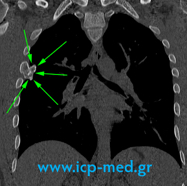

Ευμέγεθες Οστεοχόνδρωμα διαστάσεων 6,7 × 4 × 2,2 cm , με σχήμα ακανόνιστο, ανώμαλο ή διφυές, στην 4η δεξιά πλευρά (προσθιοπλάγια μοίρα) ενός 26χρονου άρρενος μη–καπνιστού, αθλητού. Τυχαίο ακτινολογικό εύρημα.

Με Πράσινα βέλη: ο Όγκος (οστεοχόνδρωμα).

Με Κίτρινα βέλη: Υγιής μοίρα της πλευράς (καθώς και όριο χειρουργικής εκτομής “επί υγιούς”).